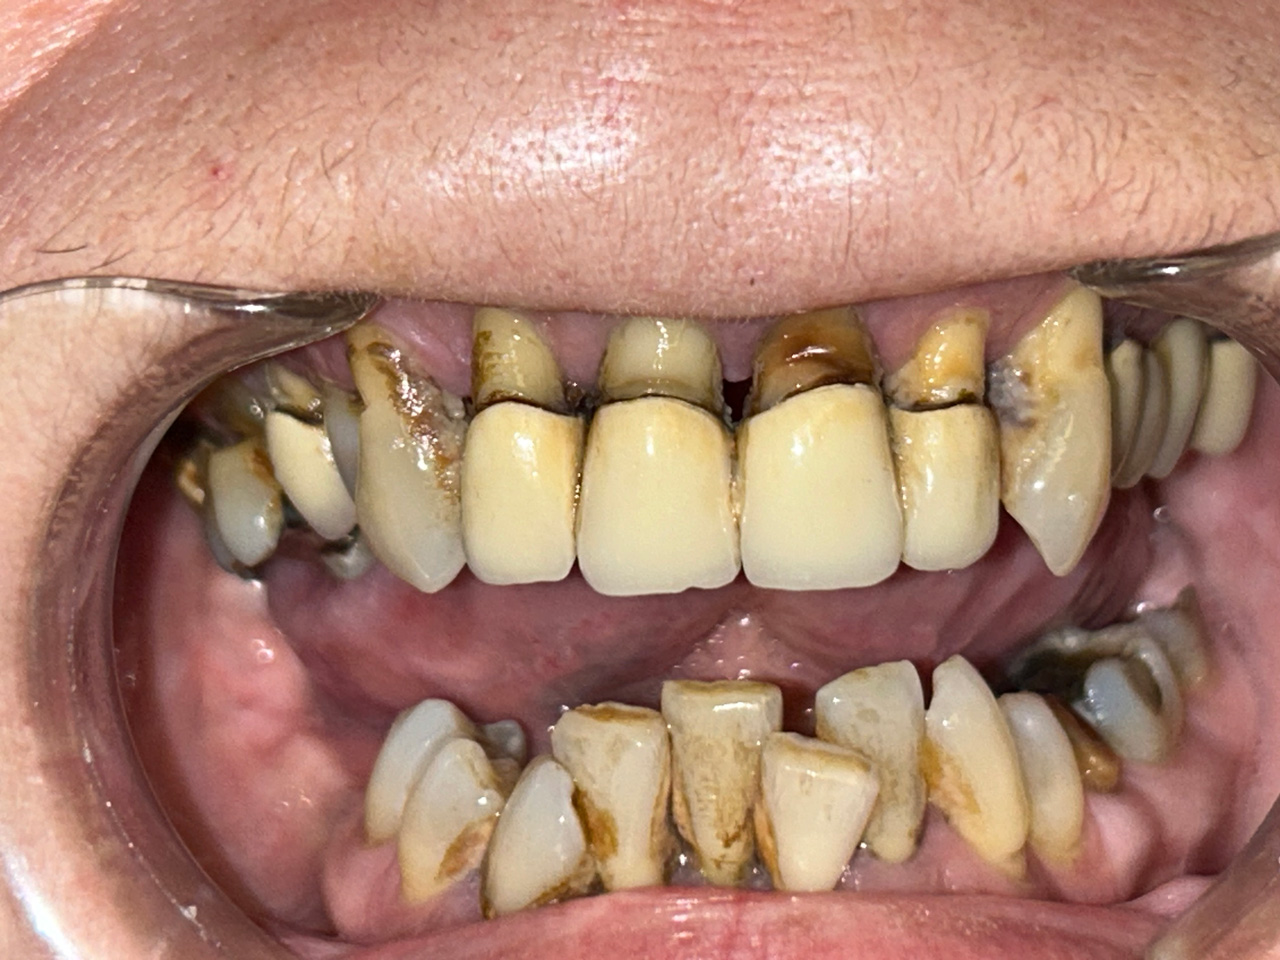

Elhanyagolt fogsor cseréje 2 nap alatt

2 nap alatt varázsoltuk ezt a szép esztétikus alsó, felső körhídat implantátumokkal megtámasztva a korábban elhanyagolt szájba. Az 1. nap 26 fogat távolítottunk el, mert annyira rossz állapotban voltak, és rögtön azonnal terhelhető IHDE svájci implantátumokat raktunk be, fentre 8, lentre 6 darabot. A sebeket összevarrtuk és intraorális szkennerrel digitális lenyomatot vettünk. 2 nap múlva pedig beragasztottuk a kész PMMA műanyag körhidakat. Dr. Kelemen Péter és a Symbion Fogtechnika munkája.